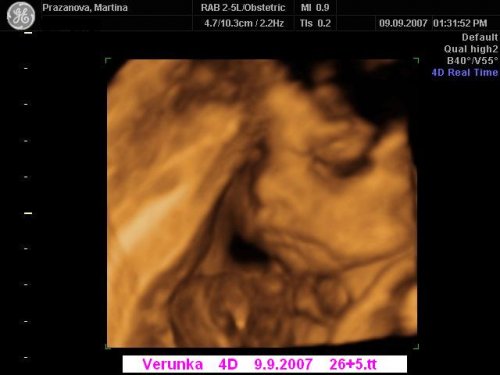

Už se nemůžeme dočkat 1.5....jdeme na 4D UTZ, tak doufám, že se nám ten náš klučík ukáže v plné své kráse 🙂))